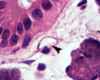

Identify the structure:

continuous capillary

Key features of continuous capillaries:

- tight junctions;

- Pinocytotic vesicles (transcytosis) enable substances to pass from the lumen to the CT